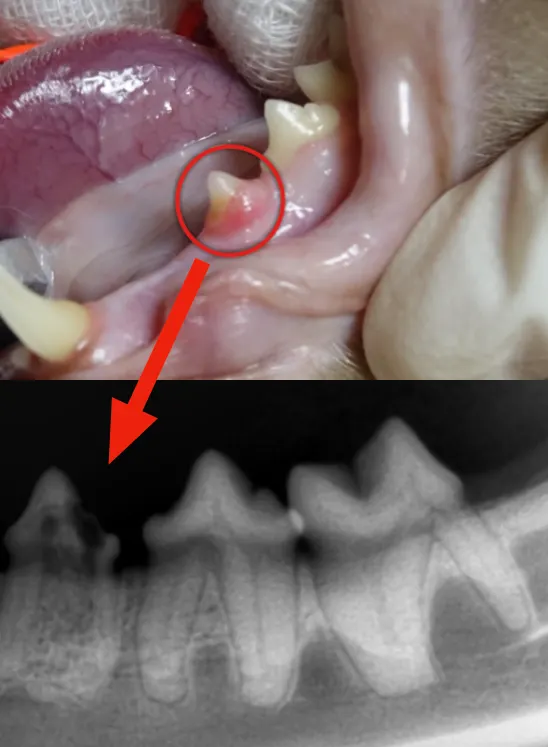

위에 사진에서 동그라미 부위의

치아를 잘 관찰해주세요~

위의 사진처럼 육안검사상

큰 문제가 없어 보이는

치아의 경우에도

치아 방사선 검사상

치아 흡수성 병변이

보이는 것을 알 수 있습니다.